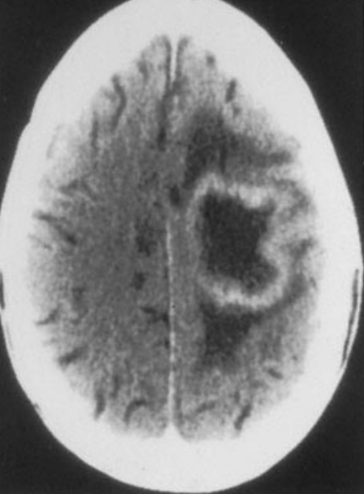

What is this?

-pt has AIDs

Which organism caused this?

Toxoplasma gondii